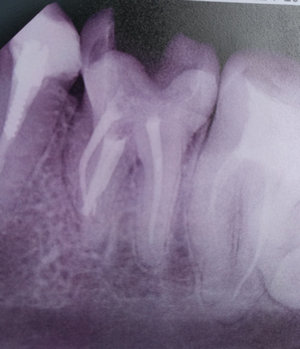

Сделали снимок, на снимке оказалось, что под семеркой на удалении 5 мм от корней потемнение (воспаление) размером 5 мм на 4 мм. Врач советует, что лучшим вариантом будет удаление зуба и установка импланта, так как лечение только будет дороже из-за того, что корень зуба изогнут и очень сложно выполнить чистку каналов (сейчас пролечим, а через полгода опять будет воспаление).